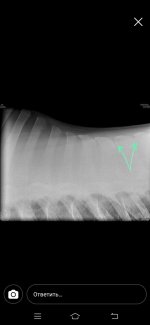

Нужна помощь. Лошадь 5 лет (6 лет будет в июне) обнаружили сегодня по ренгену спины серьезные проблемы.

По ренгену увидели что у лошади срослось костистые отростки ,образовалась хрящевая ткань. Как мне объяснили при ранней заездки лошади оказывалась не правильная работа принципе, был тяжелый всадник, не правильно подобраное седло. Из за этих факторов у лошади терлись друг об друга позвонки, произошло смещение + срастание. Как мне сказали теперь на лошади нельзя прыгать и нести верховные нагрузки. Только если будет хорошее седло +гель+меховушка ,и то если всадник не тяжелый и только (шаг, рысь, галопом в небольшом потвренмени количеству). В чем суть вопроса кто то может посоветовать подкормки или что то подобное

Как мне сказали это ничем не исправить уже...но можно что нибудь давать для поддержания формы или колоть (а вот что не сказали т.к. Врачи не специализировался именно на этом) есть ли тут ветеринары? Позже могу прикрепить снимки (когда скинут мне их на почту) спасибо всем заранее

По ренгену увидели что у лошади срослось костистые отростки ,образовалась хрящевая ткань. Как мне объяснили при ранней заездки лошади оказывалась не правильная работа принципе, был тяжелый всадник, не правильно подобраное седло. Из за этих факторов у лошади терлись друг об друга позвонки, произошло смещение + срастание. Как мне сказали теперь на лошади нельзя прыгать и нести верховные нагрузки. Только если будет хорошее седло +гель+меховушка ,и то если всадник не тяжелый и только (шаг, рысь, галопом в небольшом потвренмени количеству). В чем суть вопроса кто то может посоветовать подкормки или что то подобное

Как мне сказали это ничем не исправить уже...но можно что нибудь давать для поддержания формы или колоть (а вот что не сказали т.к. Врачи не специализировался именно на этом) есть ли тут ветеринары? Позже могу прикрепить снимки (когда скинут мне их на почту) спасибо всем заранее